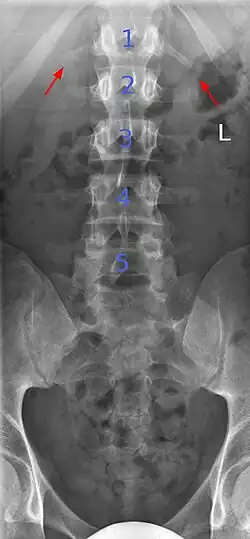

Butterfly vertebrae

Butterfly vertebrae have a sagittal cleft through the body of the vertebrae and a funnel shape at the ends. This gives the appearance of a butterfly on an x-ray. It is caused by persistence of the notochord (which usually only remains as the center of the intervertebral disc) during vertebrae formation. There are usually no symptoms. There are also coronal clefts mainly in skeletal dysplasias such as chondrodysplasia punctata. In dogs, butterfly vertebrae occur most often in Bulldogs, Pugs, and Boston Terriers.[10]

-

Butterfly vertebra (red). Normal vertebra for comparison (blue). -